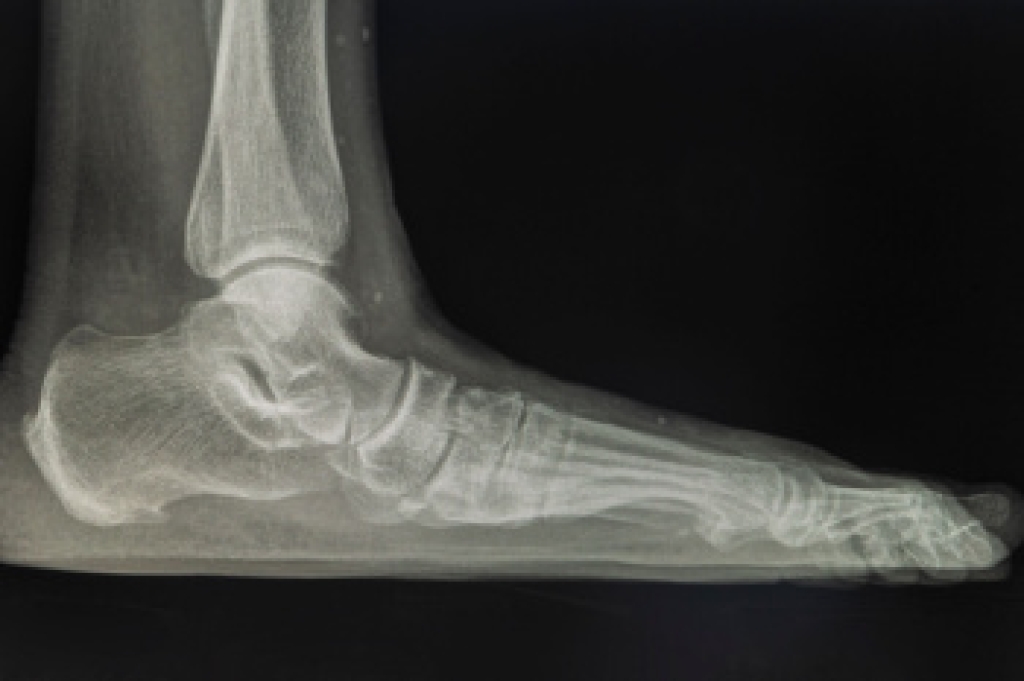

Wearing high heels may enhance height and appearance, but frequent use can lead to significant foot problems. The unnatural position of the foot places pressure on the toes and forefoot, often causing bunions and hammertoes. The elevated heel strains the Achilles tendon, leading to Achilles tendonitis, and increases tension on the plantar fascia, resulting in plantar fasciitis. Over time, these conditions can cause chronic pain and limit mobility. A podiatrist can assess the damage, relieve discomfort, and recommend supportive footwear or custom orthotics. If you have pain from wearing high heels, it is suggested that you visit a podiatrist who can treat various foot conditions, and guide you on how to choose heels that are better for your feet.

What Kinds of Foot Problems Can Develop from Wearing High Heels?

- Plantar Fasciitis